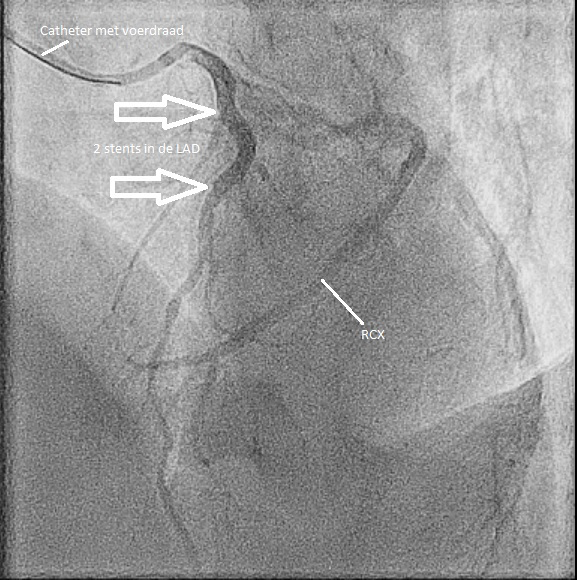

Video 3 en 4 – LAD na stenting (2 drug eluting stents zijn geplaatst). De LAD heeft weer goede flow.

Figuur 4: Met twee pijlen wordt aangegeven waar de stents zich bevinden.